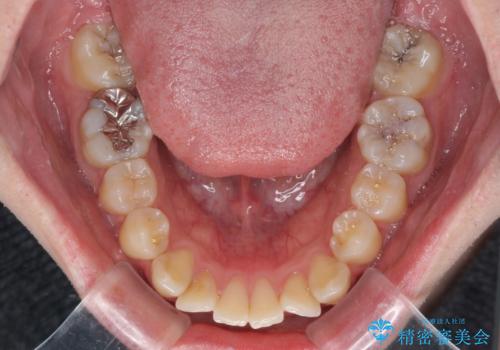

- 上下前歯のデコボコを気にして来院された患者様です。

マウスピース矯正でもワイヤー矯正でも対応可能でしたが、インビザラインによる自己管理が煩わしいとのことで、ワイヤー装置にて矯正治療を行うこととしました。

口元はやや突出感がありましたが抜歯矯正をするほどではないため、舌突出癖を改善するトレーニングをしっかりと行っていただき、現在よりも唇が閉じやすい位置に仕上げていくこととしました。

下顎前歯が思っていた以上に動きが悪く、想定よりも期間がかかってしまいました。